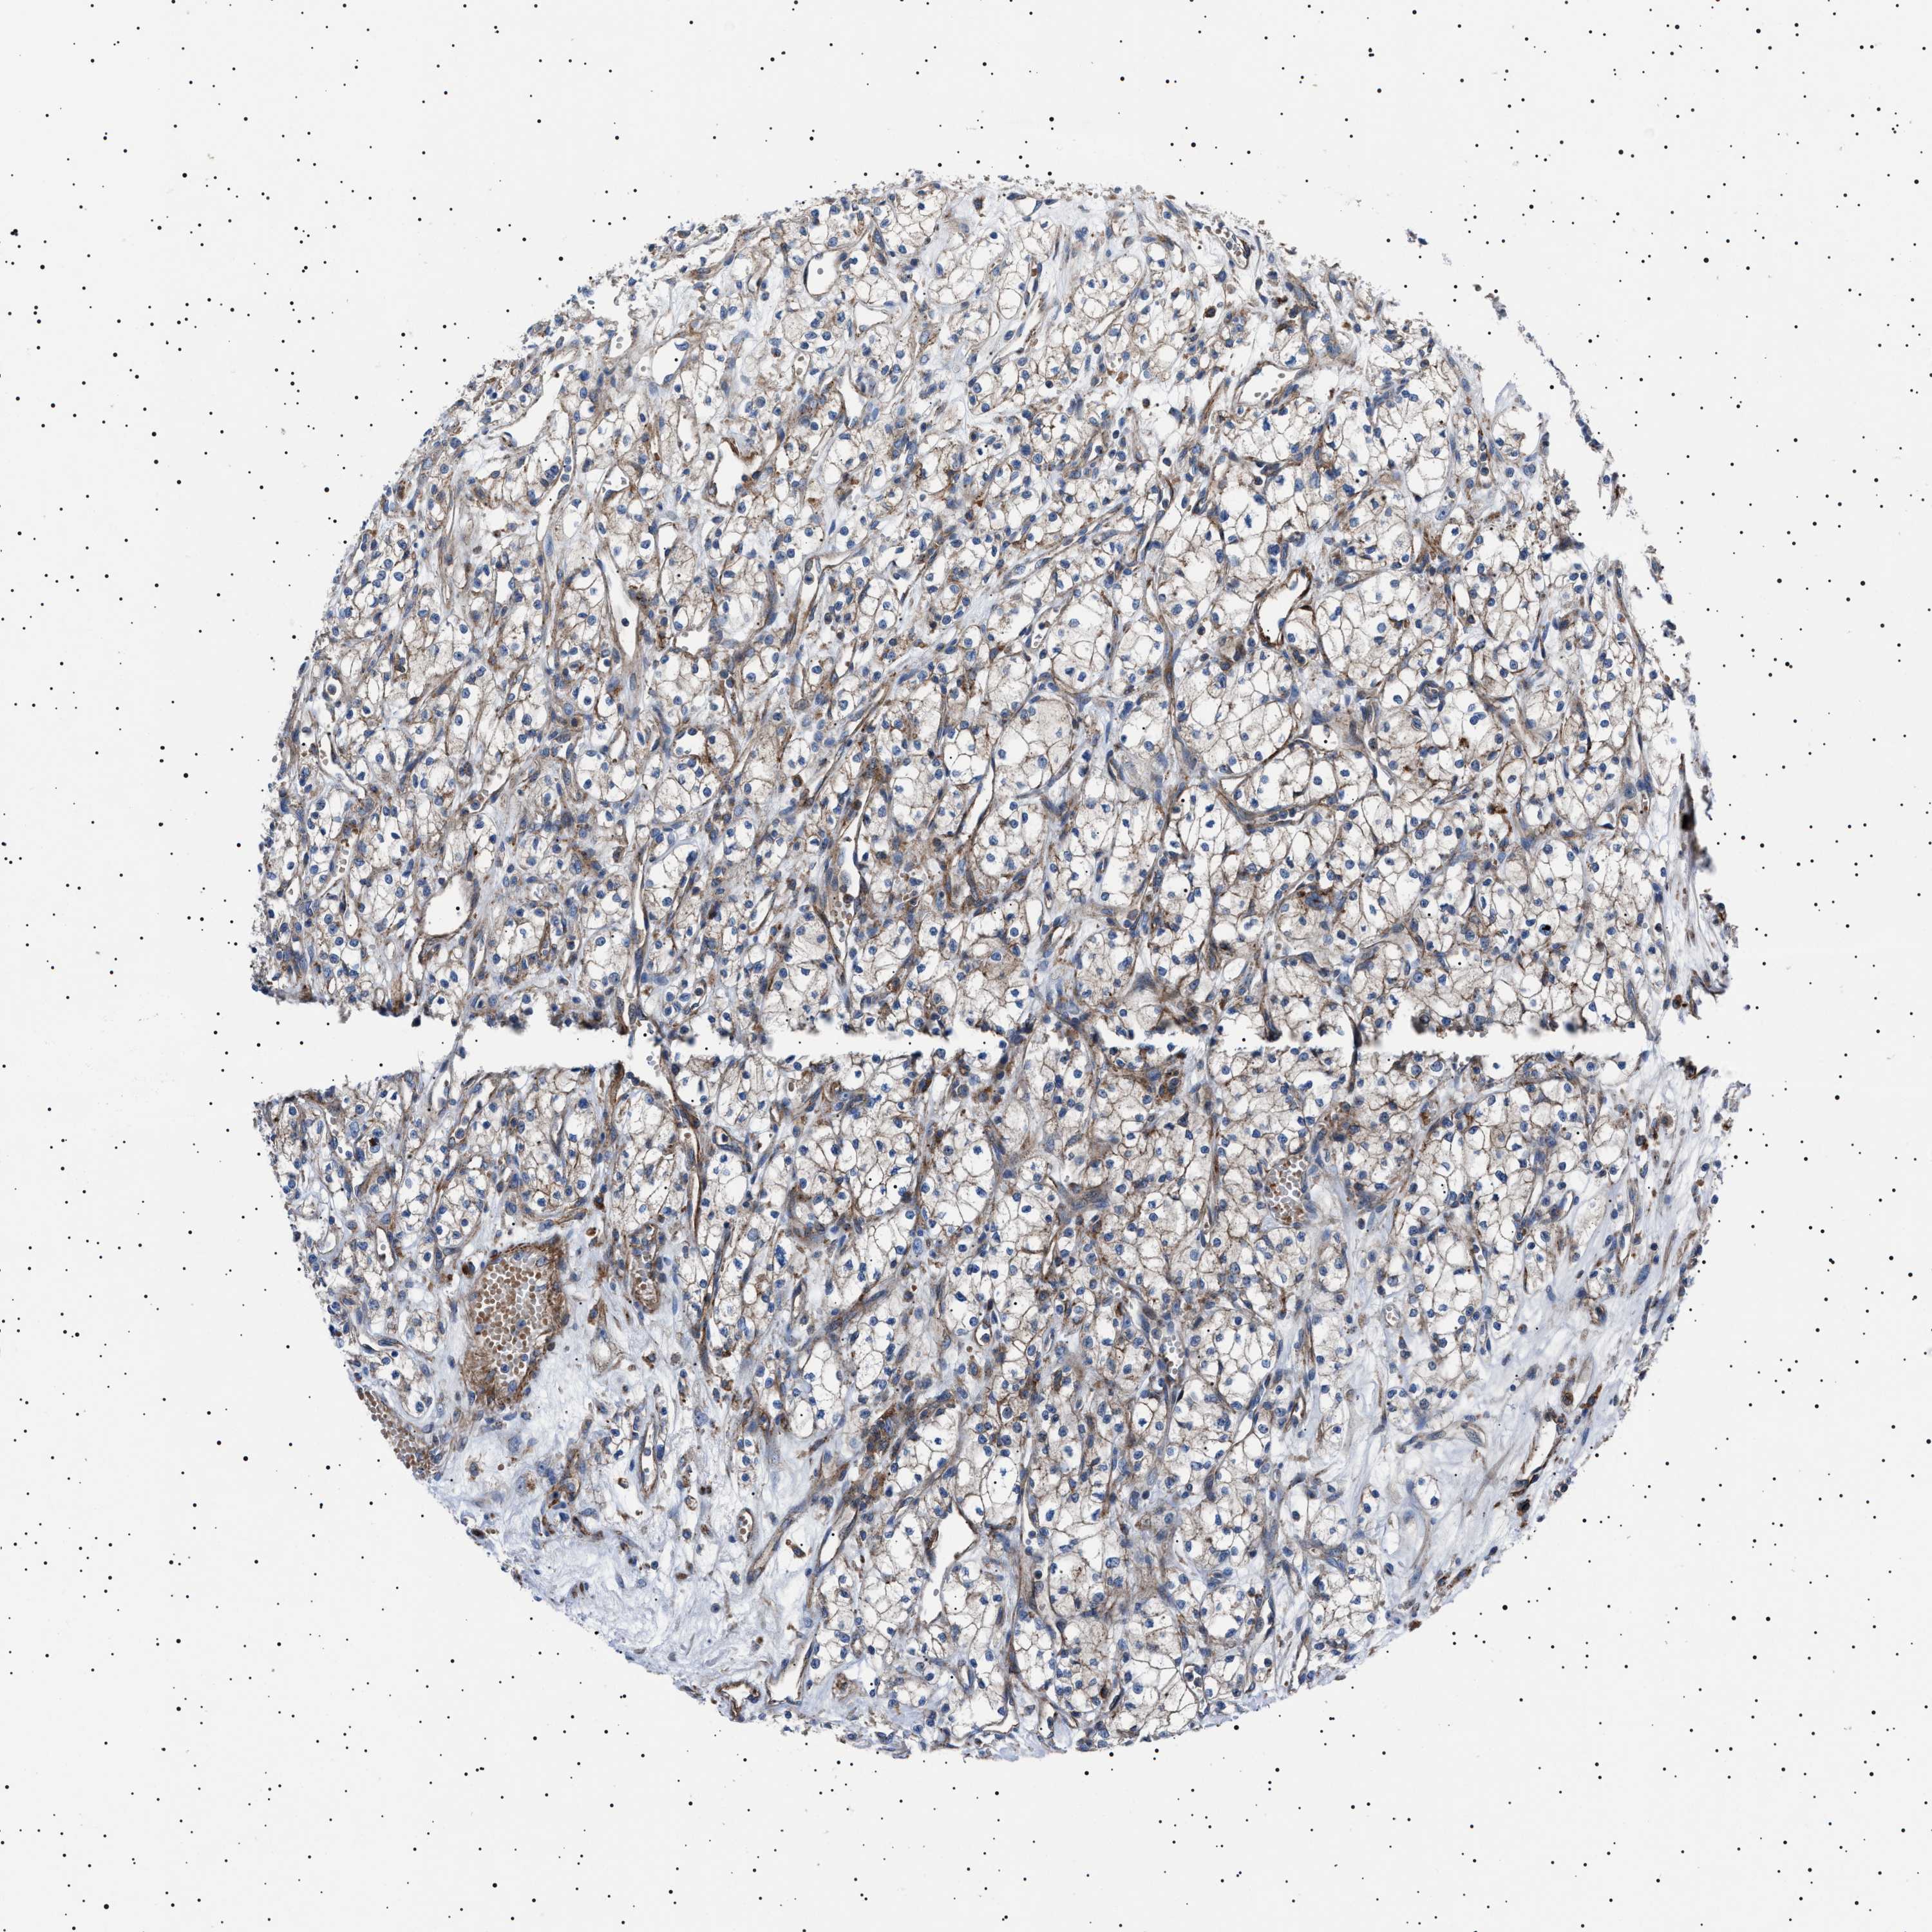

KIDNEY RENAL CLEAR CELL CARCINOMA (TCGA) - Interactive survival scatter ploti

The Survival Scatter plot shows the clinical status (i.e. dead or alive) for all individuals in the patient cohort, based on the same data that underlies the corresponding Kaplan-Meier plots. Patients that are alive at last time for follow-up are shown in blue and patients who have died during the study are shown in red.

The x-axis shows the expression levels (FPKM) of the investigated gene in the tumor tissue at the time of diagnosis. The y-axis shows the follow-up time after diagnosis (years). Both axes are complimented with kernel density curves demonstrating the data density over the axes. The top density plot shows the expression levels (FPKM) distribution among dead (red) and alive patients (blue). The right density plot shows the data density of the survived years of dead patients with high and low expression levels respectively, stratified using the cutoff indicated by the vertical dashed line through the Survival Scatter plot. This cutoff is automatically defined based on the FPKM cutoff that minimizes the p-score. The cutoff can be changed by dragging the vertical line or by entering a cutoff value in the square labeled "Current cut-off".

Under the Survival Scatter plot the p-score landscape (black curve; left axis) is shown together with dead median separation (red curve; right axis). Dead median separation is the difference in median mRNA expression between patients who have died with high and low expression, respectively. It is calculated as follows: median FPKM expression of dead patients with high expression - median FPKM expression of dead patients with low expression. This is intended to aid the user in visually exploring custom cutoffs and the associated p-scores and dead median separation.

Individual patient data is displayed and can be filtered by clicking on one or more of the category buttons on the top of the page. Categories describing expression level and patient information include: high, low, alive, dead, female, male and tumor stages. The scale of the x-axis can be toggled between linear and log-scale by clicking on the "x log" button. Mouse-over function shows TCGA ID, patient information and mRNA expression (FPKM) for each patient.

& Survival analysisi

Kaplan-Meier plots summarize results from analysis of correlation between mRNA expression level and patient survival. Patients were divided based on level of expression into one of the two groups "low" (under cut off) or "high" (over cut off). X-axis shows time for survival (years) and y-axis shows the probability of survival, where 1.0 corresponds to 100 percent.

NEU1 is potential prognostic, high expression is favorable in Kidney Renal Clear Cell Carcinoma (TCGA)

Best expression cut offi

Based on the FPKM value of each gene, patients were classified into two groups and association between prognosis (survival) and gene expression (FPKM) was examined. The best expression cut-off refers the FPKM value that yields maximal difference with regard to survival between the two groups at the lowest log-rank P-value. Best expression cut-off was selected based on survival analysis .

When clicking on this number, the vertical dashed line indicating cut-off, the interactive survival plot, and the Kaplan-Meier curve will be adjusted to show results based on the best expression cut-off.

: 1.86

P scorei

Log-rank P value for Kaplan-Meier plot showing results from analysis of correlation between mRNA expression level and patient survival.

N/A

TCGA RNA samplesi

RNA-seq data is reported as average FPKM (number Fragments Per Kilobase of exon per Million reads), generated by the The Cancer Genome Atlas (TCGA) .

Normal distribution across the dataset is visualized with box plots, shown as median and 25th and 75th percentiles. Points are displayed as outliers if they are above or below 1.5 times the interquartile range. FPKM values of the individual samples are presented next to the box plot.

Average pTPM 1.3

Number of samples 521